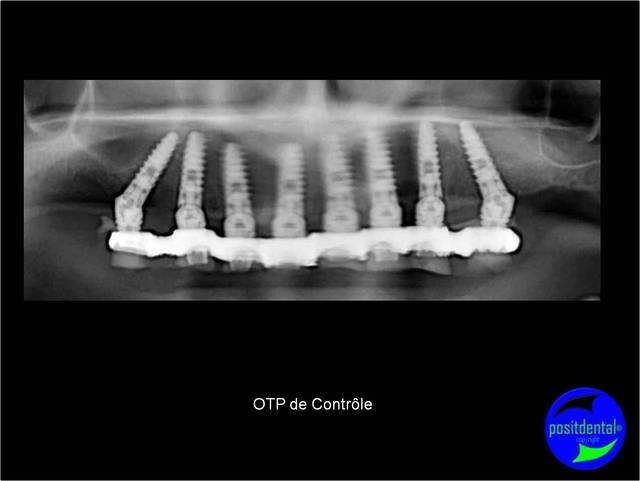

jumpingjackflash écrivait:

--------------------------

> c'est joli les images numériques mais une radio de temps en temps c'est

> instructif aussi

et indispensable